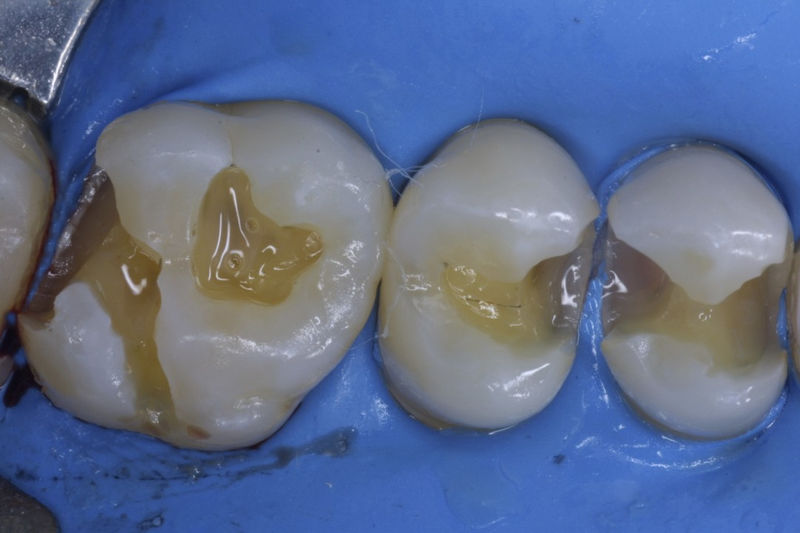

Restauraciones fabricadas en el laboratorio con materiales estéticos, los cuales cubren de manera parcial dientes posteriores. Se utilizan primariamente para restaurar dientes con caries, fracturas y/o defectos amplios. Para poder enviar el caso al laboratorio se toman impresiones utilizando materiales de impresión o técnicas modernas digitales.